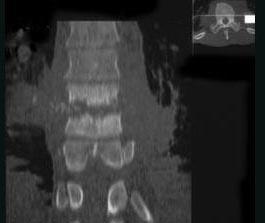

问题 女,59岁,腰背部疼痛伴低热,乏力,请结合影像学检查,选出最可能的诊断 ( )

选项 A、椎体压缩骨折 B、强直性脊柱炎 C、化脓性脊柱炎 D、脊椎结核 E、脊柱转移瘤

答案 D